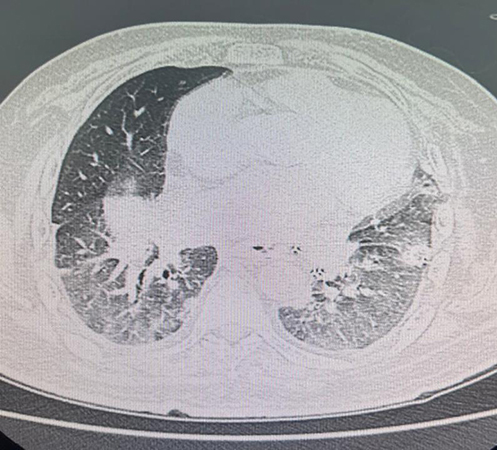

However, six weeks after transplantation, the patient presented with new-onset fatigue and a mild increase in his oxygen requirements. High-resolution computed tomography (HRCT) of the chest demonstrated bilateral ground-glass opacities (GGOs), raising concerns for potential infection, acute rejection, or early antibody-mediated rejection (AMR). Diagnostic bronchoscopy with bronchoalveolar lavage (BAL) microbiologic analysis returned negative for bacterial, mycobacterial, fungal, and viral pathogens. Repeat SAB testing, however, revealed the emergence of high mean fluorescence intensity (MFI) donor-specific antibodies (DSAs) against HLA Class II antigens: DQA1*06:01 (MFI 13,600; cutoff 1,000) and DQA1*03:01 (MFI 9,560; cutoff 1,000).